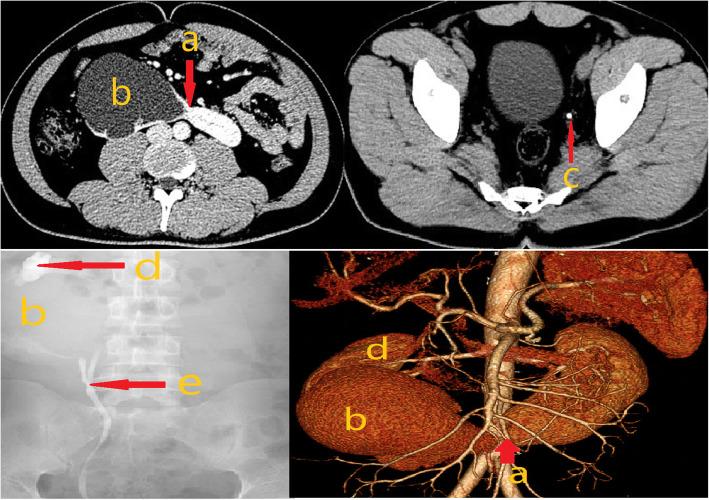

腹腔镜联合输尿管镜治疗马蹄肾合并重复肾及输尿管结石 1 例报告。

Laparoscopy combining with ureteroscopy for horseshoe kidney accompanying with duplicate kidney and a ureteral calculus: a case report.

This report documents an extremely rare case, which was treated by multiple procedures in the same operative session to accomplish laparoscopic amputation of the HSK isthmus, resection of duplicate kidney and ureteroscopic lithotripsy.

马蹄肾(HSK)是一种常见的肾脏融合畸形,约每 400-600 人中发生 1 例。此外,重复集合系统的发生率约为 0.8%。

病例介绍

本报告记录了一例极其罕见的病例,该病例在同一手术中通过多次手术进行治疗,以完成腹腔镜马蹄肾峡部切断、重复肾和输尿管镜碎石术。